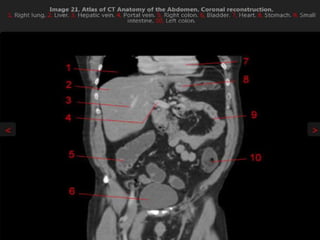

CT cross sectional anatomy.

CT – computedtomography. •Cross-sectional modality with capabilities for multiplanar reconstruction and dynamic imaging to assess vascularity •Tube rotates around the body and a circle of stationary detectors detects the penetrating x-rays forming an image.

MRI anatomy imagesof the abdomen.